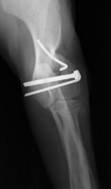

Chirurgia, ortopedia

Wykonujemy szereg zabiegów operacyjnych z zakresu chirurgii miękkiej, jak i twardej. Przeprowadzane przez nas operacje często ratują życie, a niejednokrotnie również polepszają jego jakość.

W ramach chirurgii twardej przeprowadzamy m.in. takie zabiegi jak:

• operacje stawu kolanowego po uszkodzeniu więzadła krzyżowego

• zwichnięcie stawu biodrowego, w tym resekcja główki i szyjki kości udowej

• zwichnięcia rzepek

• operacyjne leczenie złamań i zwichnięć

• amputacje kończyn

• chirurgia szczękowa